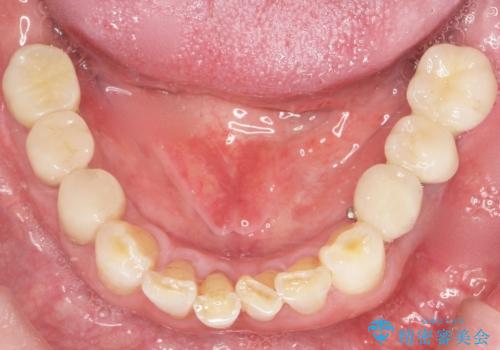

奥歯のインプラント 70代男性

- 奥歯の違和感を主訴に来院された患者様です。

精査したところ、右下の奥歯は大きなう蝕により保存不可能な状態でした。

患者様のご希望により、抜歯後インプラント治療を行いました。